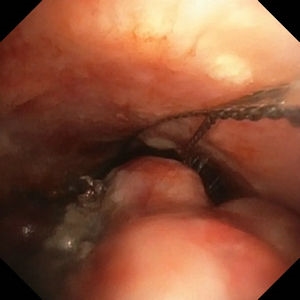

全麻下气管镜检查提示:气管管腔中段可见菜花状新生物形成,几近完全阻塞气管。病灶基底部宽大,不适宜应用硬质气管镜铲切,遂应用电圈套器圈套、氩气刀、针状电刀、冷冻(冻切及冻溶)、球囊扩张等治疗。

治疗前后对比